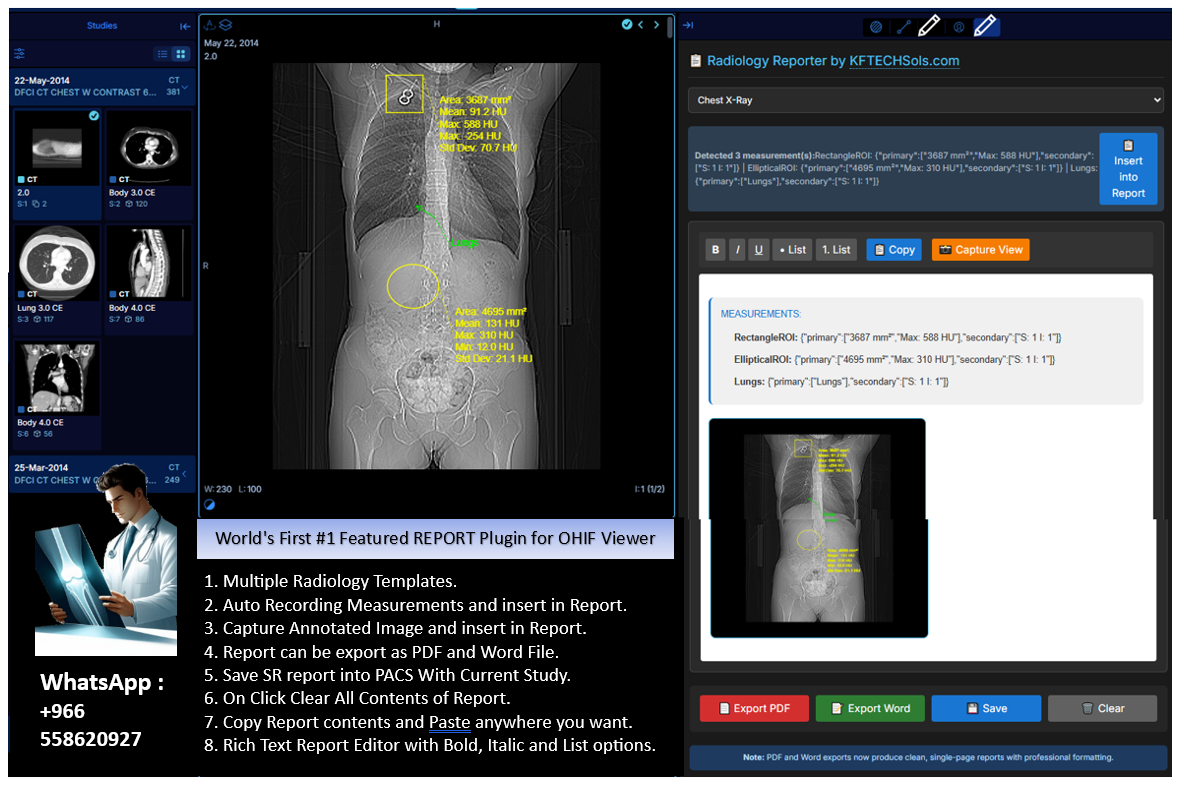

Custom Development for OHIF Dicom Viewer

The OHIF DICOM Viewer is a web-based medical imaging viewer designed to display and interpret DICOM (Digital Imaging and Communications in Medicine) images from various modalities such as X-ray, MRI, CT scans, etc.

We offer custom development of Plugins, Extentions, Modes, ViewPorts for OHIF Viewer.

Our Development Strategy :

We listent carefully to our clients for their requirements or scope of work regarding new feature development for OHIF.

After deep analysis of requirements, We send Proposal with all details Cost, Delivery Time and Technical Specifications.

After discussion and final approval, and 50% Advance confirm payment from Client, We start Development and deliver successfully

Order Strategy

- Gather Requirements.

- Send Detailed Proposal.

- Start Development.

Extensions Types

- Tools Extensions.

- Reporting Extensions.

- Modes/ViewPorts.

DEV. Extensions

- CT Ration Finder.

- Speech Dictation.

- Reporting with Annotated Image and Measurements Auto Embedding.